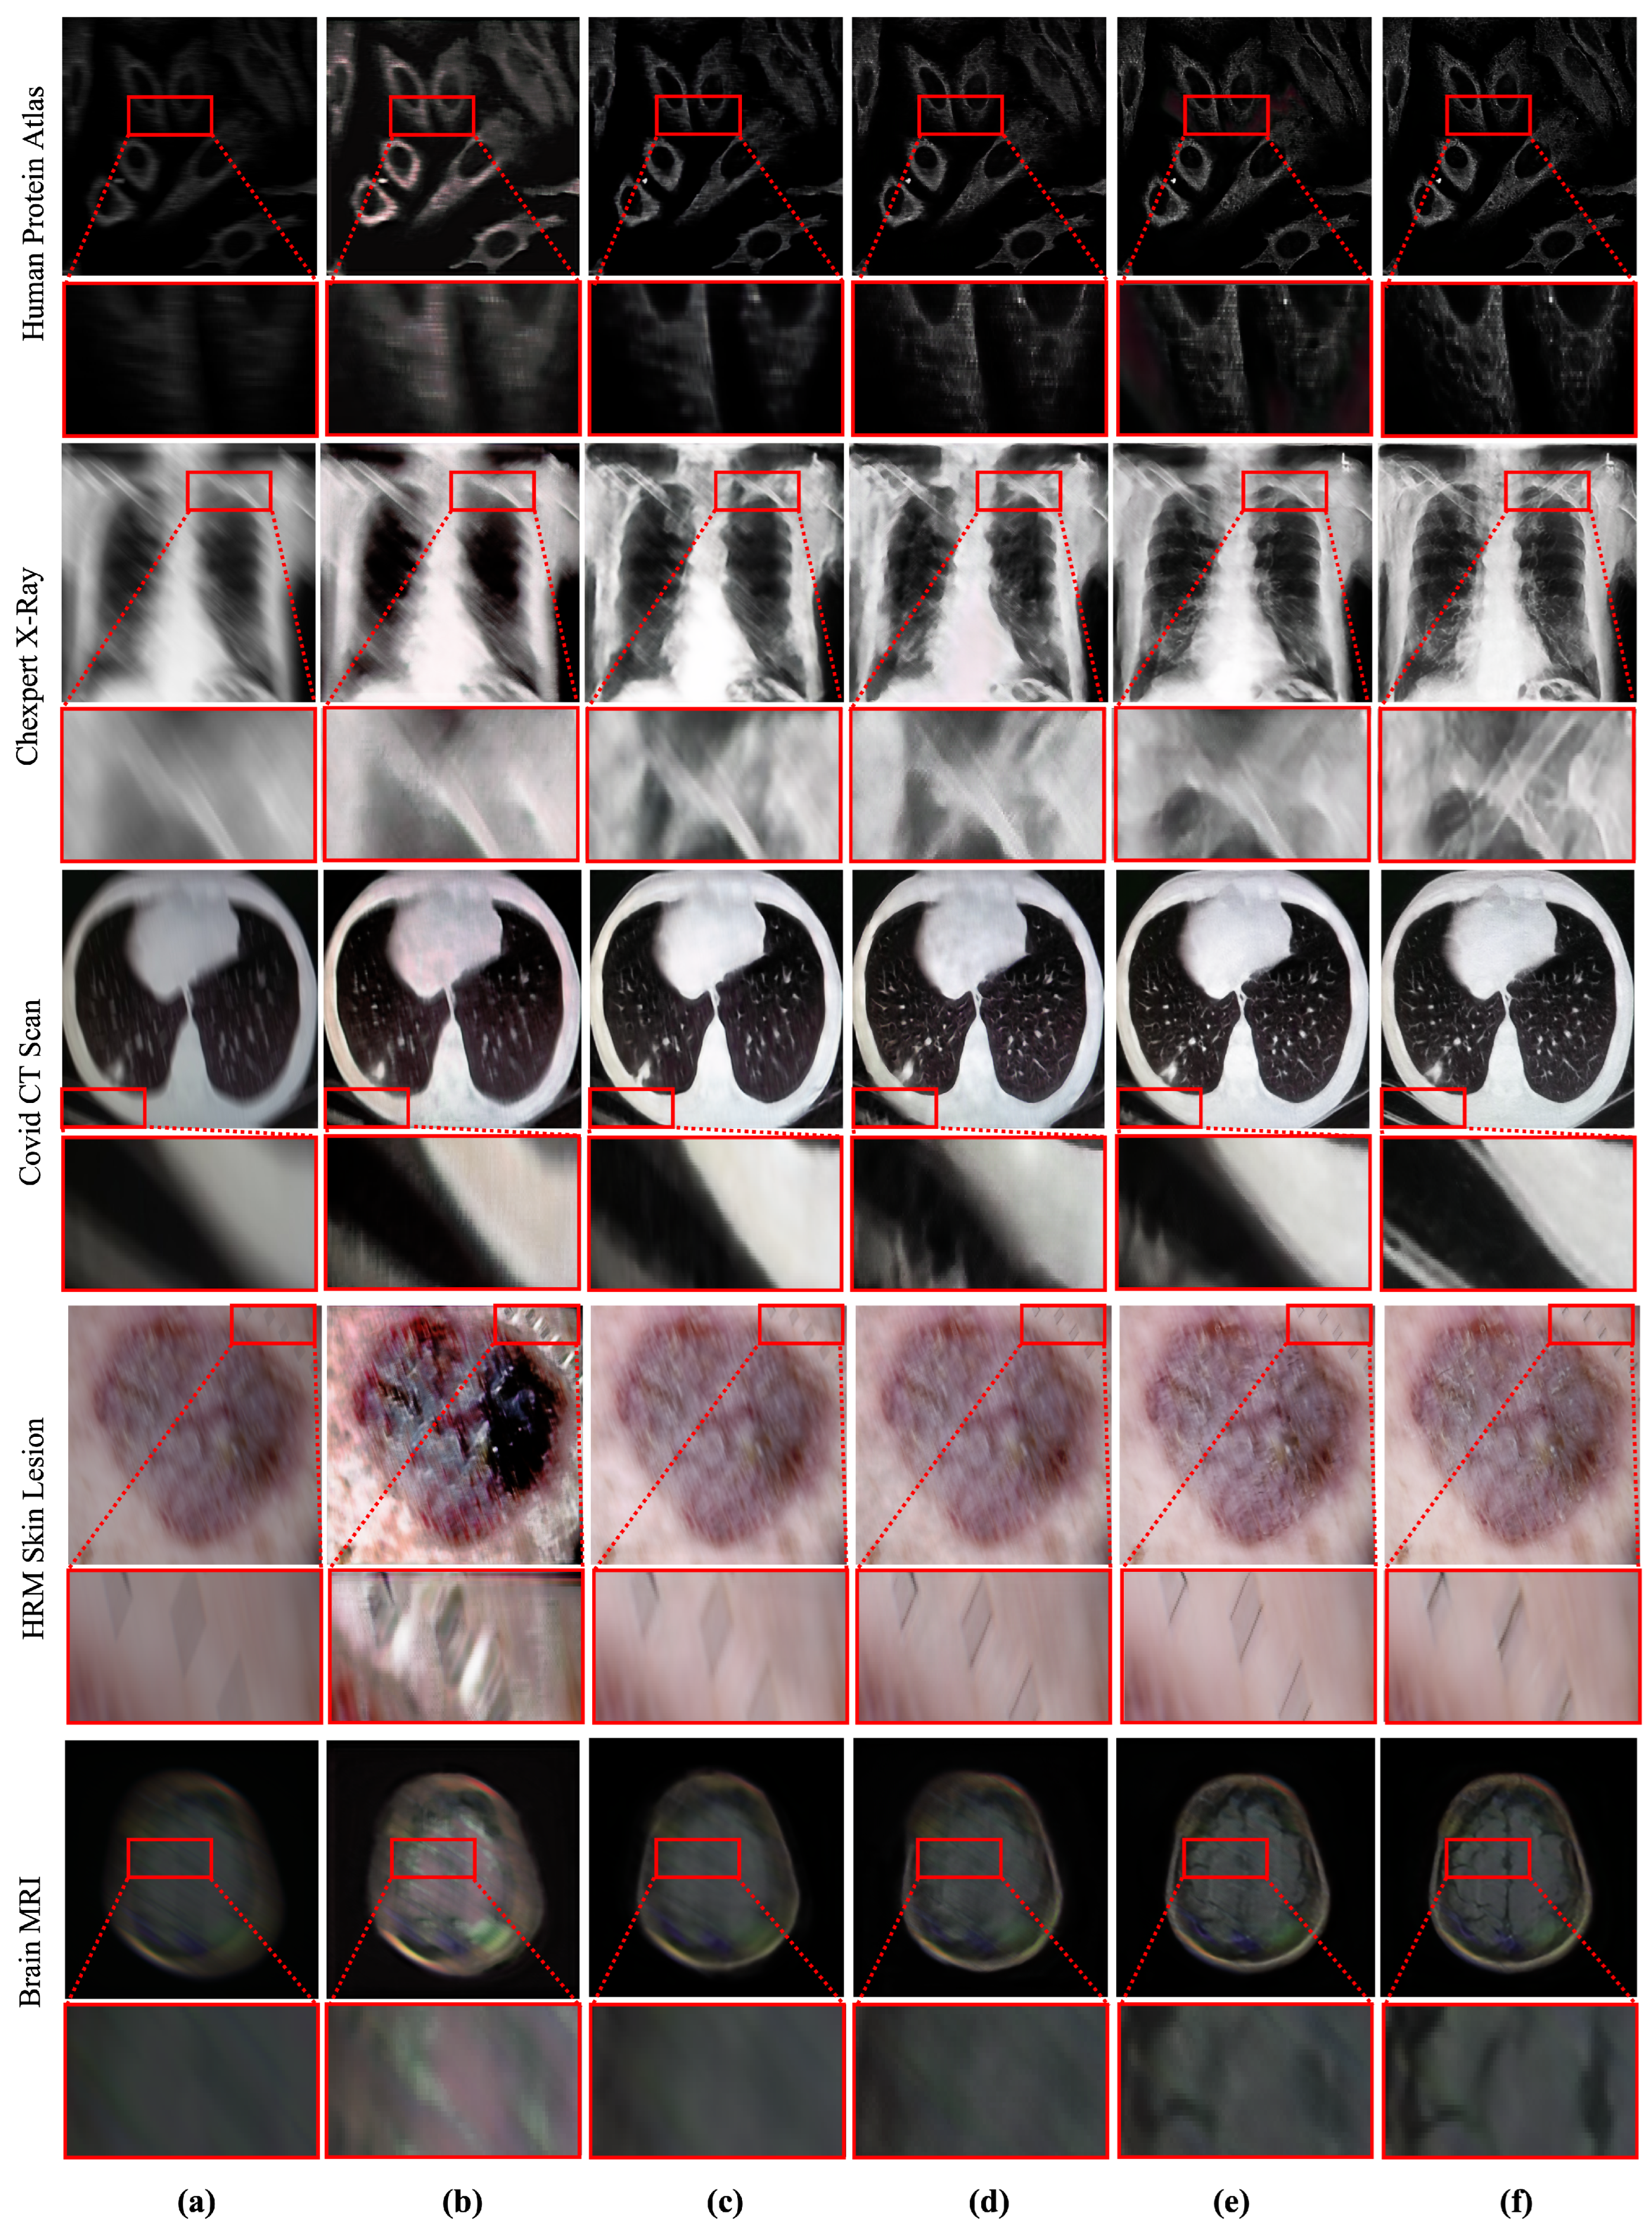

4.1.2. Qualitative Comparison

4.2. Deblurring in Computer-Aided Diagnosis